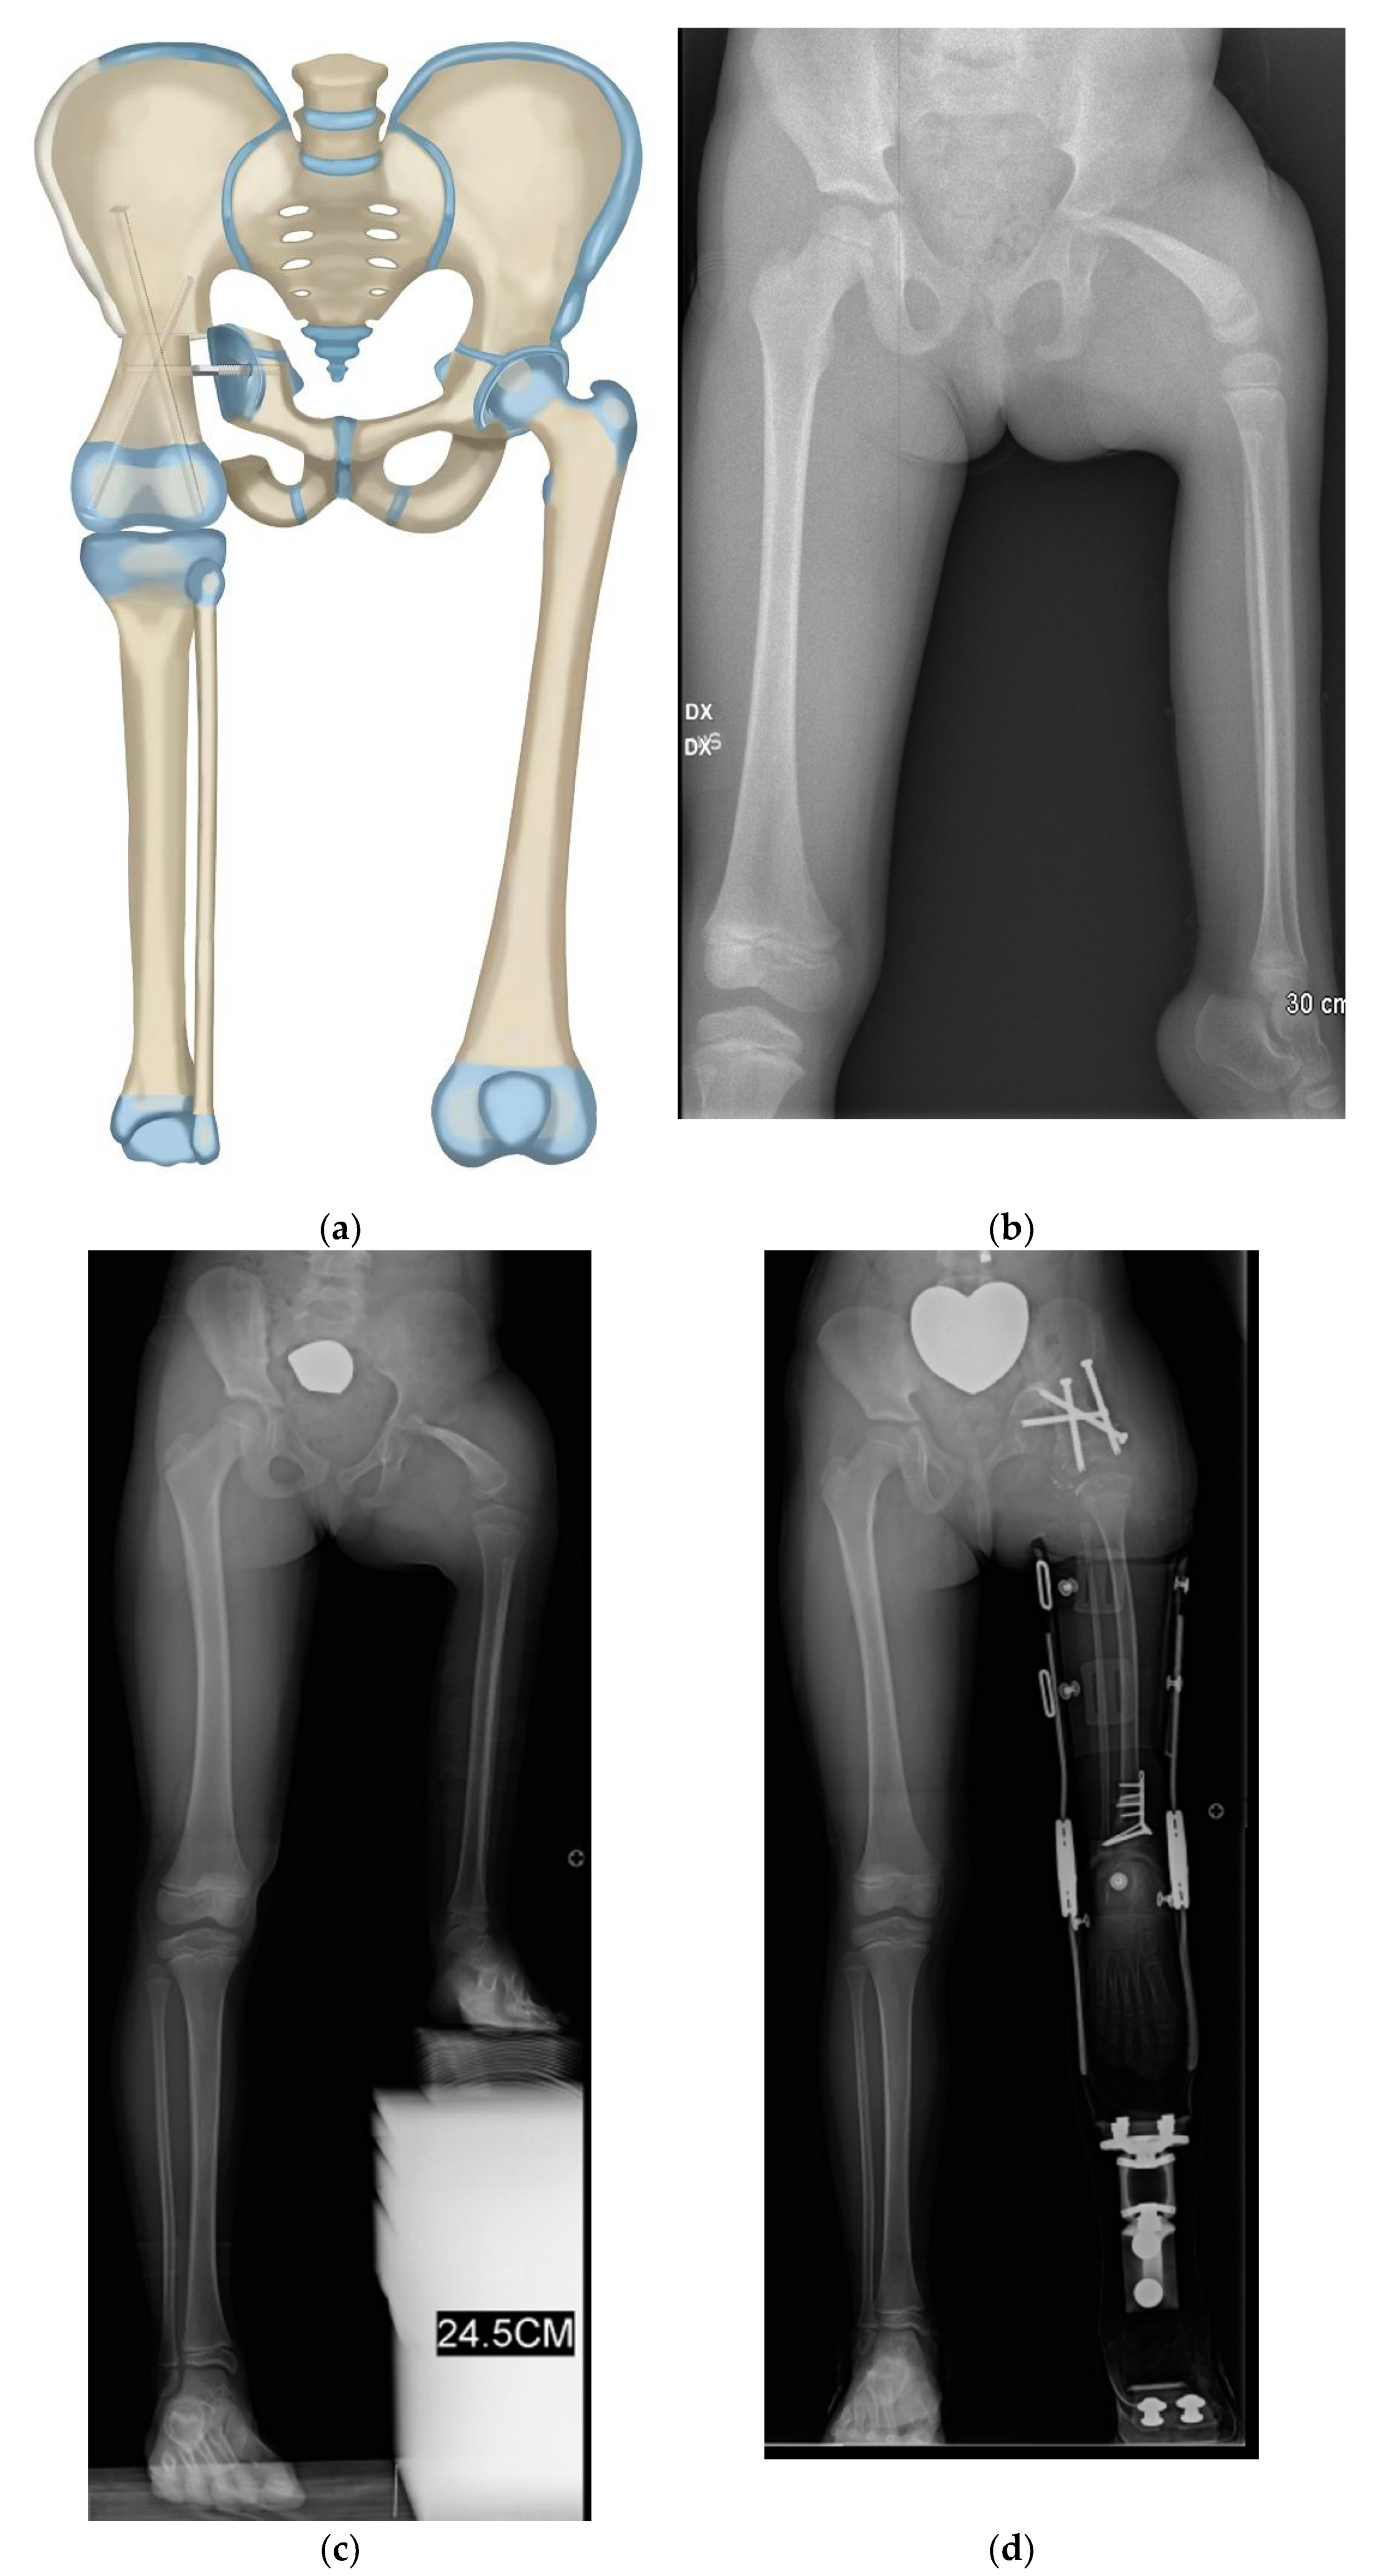

Figure 2.

(a) Illustration of CFD Paley type 3 (a or b), (b) Illustration after Brown rotationplasty for Paley type 3 (a or b), (c) AP pelvis x-ray of 14-year-old boy with Paley type 3b CFD, (d) Preop standing erect leg x-ray of same boy, showing that the ankle is at the level of the opposite knee (incidentally this patient also has multiple osteochondromas), (e) AP pelvis radiograph in same boy, 7 years after healed Brown rotationplasty, (f) Sanding radiograph with prosthetic 7 years after Brown rotationplasty with supramalleolar osteotomy for ankle realignment. Clinically he has excellent gait and function.

Figure 3.

(a) Paley–Brown Rotationplasty illustration for Paley type 3 (a or b), (b) AP pelvis radiograph in 3-year-old girl with Paley type 3a CFD, (c) Standing long radiograph showing the left ankle is at the level of the right knee, (d) Standing long radiograph two years after Paley–Brown rotationplasty. The ankle is at the level of the opposite distal femoral physis (level of knee center of rotation). Clinically she has excellent gait and function.